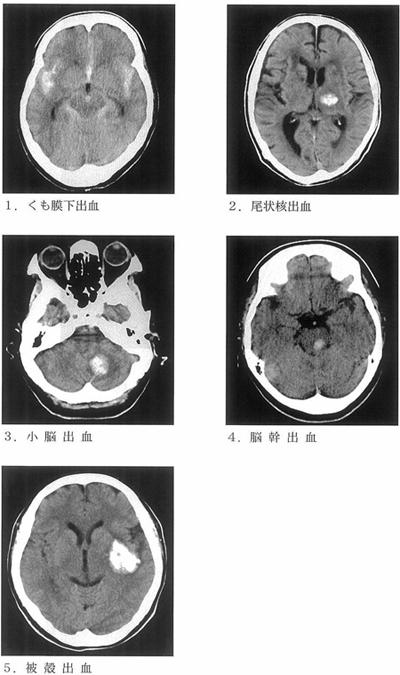

脳出血時の頭部CTを示す。誤っているのはどれか。

1

くも膜下出血

2

尾状核出血

3

小脳出血

4

脳幹出血

5

被殻出血